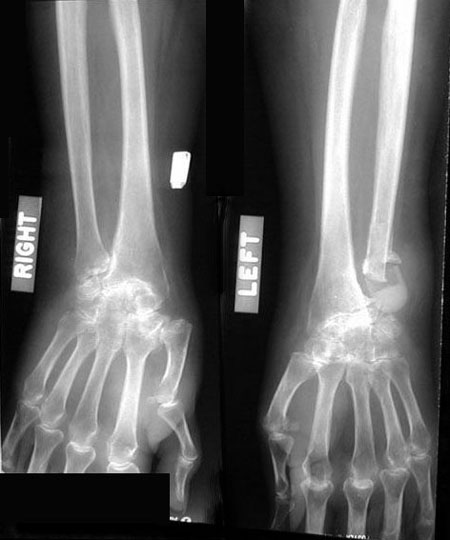

48 year old Nurse, with long

history of rheumatoid arthritis presents with cough and shortness of

breath for the past two months. She is on 15 mgm of Prednisone daily.

Diagnosis

Rheumatoid Pleural Effusion